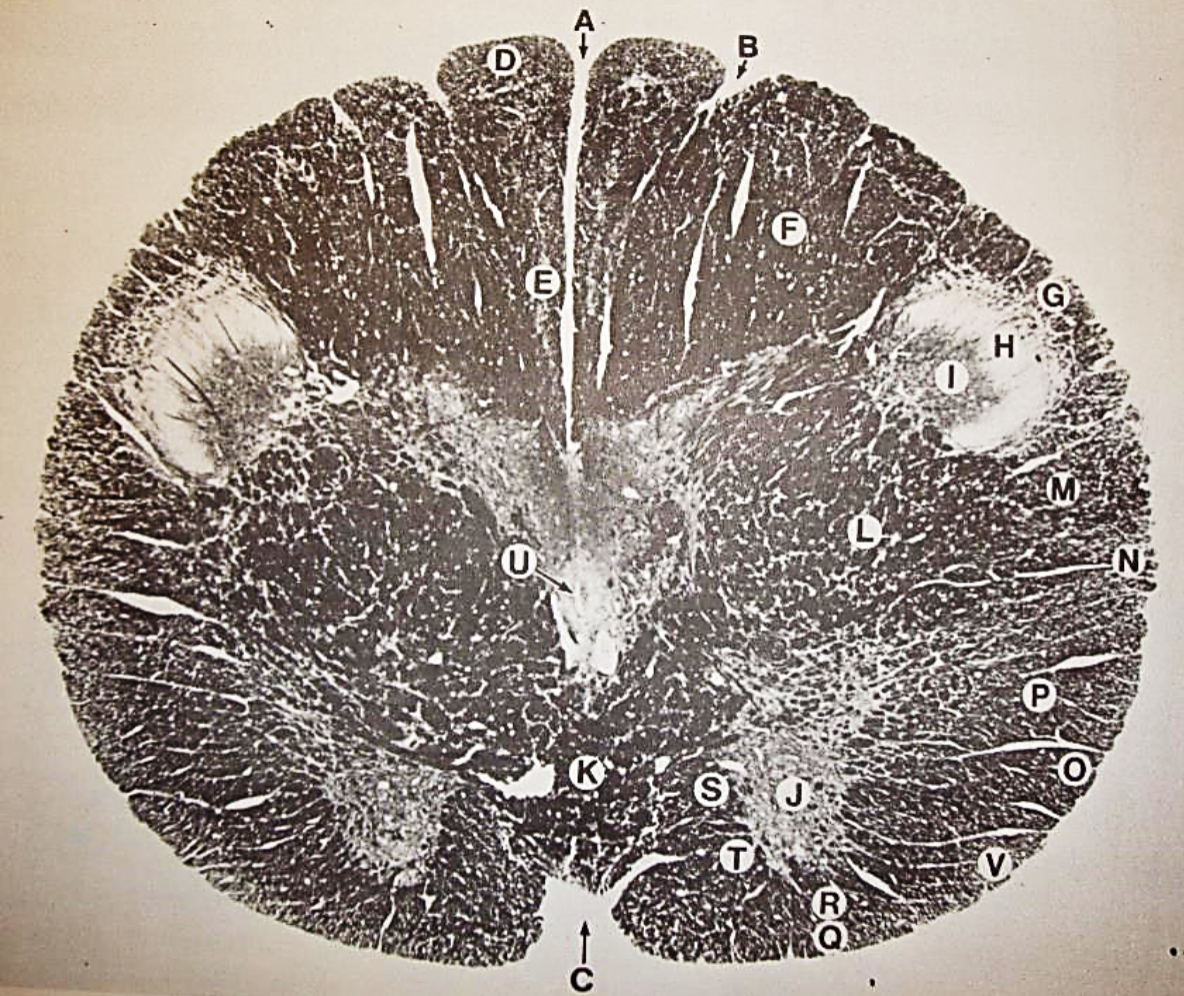

A

fasciculus gracilis

B

gracile nucleus

C

fasciculus cuneatus

D

cuneate nucleus

F

internal arcuate fibers

G

decussation of internal arcuate fibers

H

medial lemniscus

I

hypoglossal nucleus

J

dorsal motor nucleus vagus

K

solitary fasciculus

L

solitary nucleus

M

dorsal longitudinal fasciculus

N

spinal trigeminal tract

O

spinal trigeminal nucleus

P

posterior spinocerebellar tract

Q

anterior spinocerebellar tract

R

spinal lemniscus

S

lateral vestibulospinal tract

T

rubrospinal tract

U

lateral reticular nucleus

V

medial accessary olivary nucleus

W

pyramidal (corticospinal) tract

X

arcuate nucelus

Y

medial longitudinal fasciculus

Z

tectospinal tract

a

fascicles of hypoglossal nerve